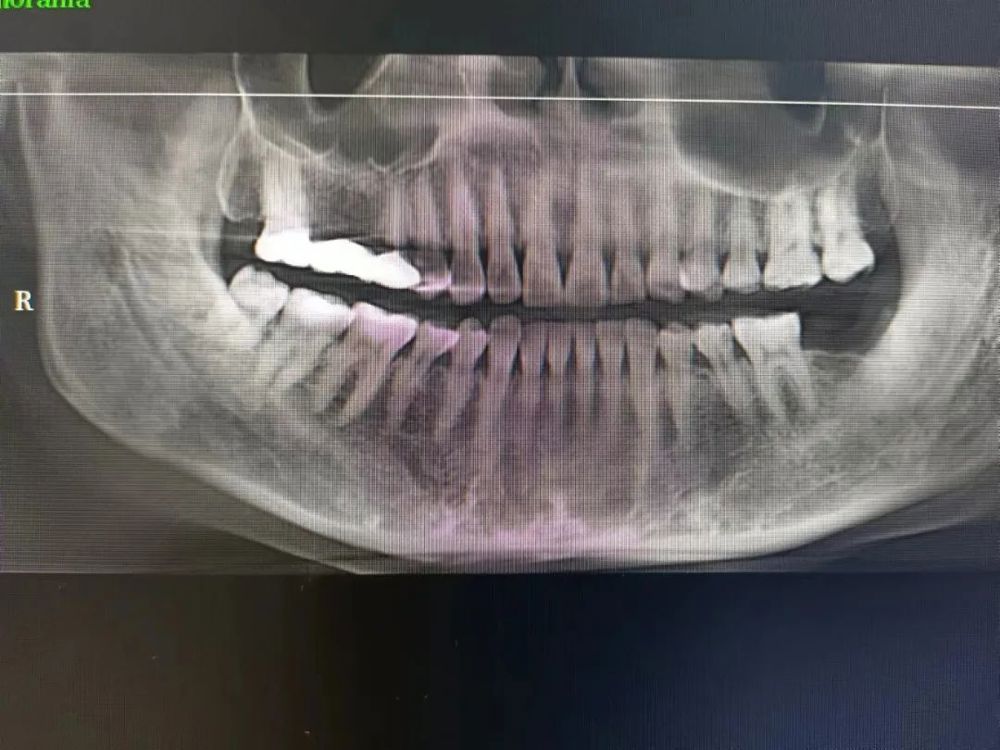

案例一

种植前 种植后